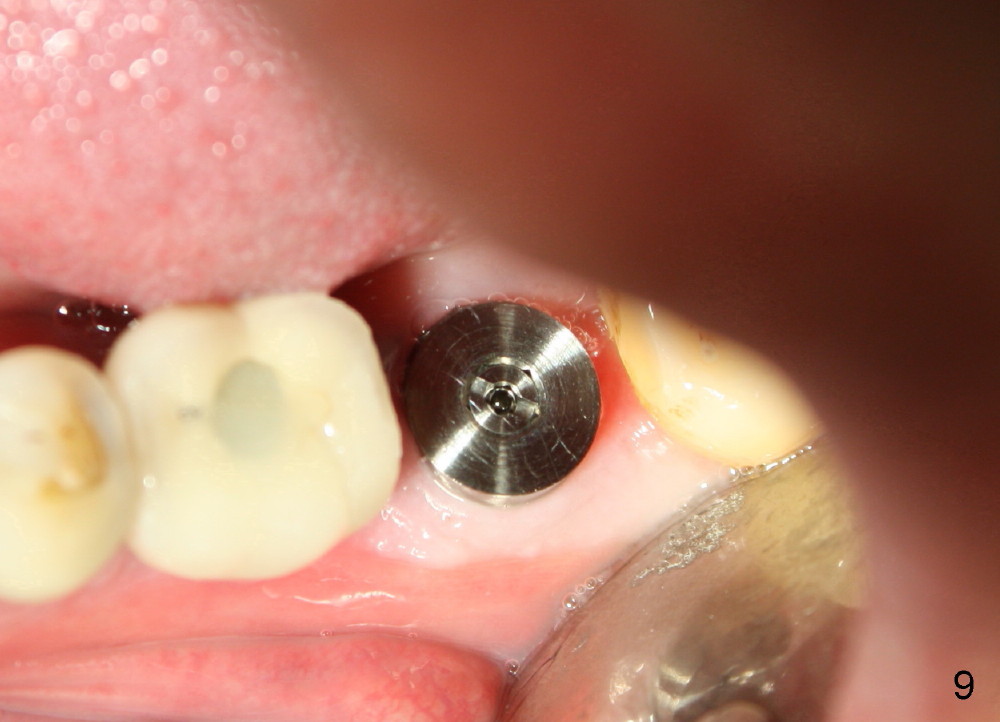

A 63-year-old man has lost a crown from the tooth #18 (Fig.1), which is tender to percussion. The margin is subgingival.

The septum of the socket is thin (Fig.3*), and easily removed, leaving a large socket. Osteotomy is initiated with 2 mm pilot drill in the middle of the socket, slightly mesiolingual, since the buccal and distal bone is low and defective. Reamers (2.5 to 4 mm in diameter) are sequentially used to enlarge osteotomy and harvest autogenous bone (Fig.4 (3 mm reamer in place). When 5 mm tap is placed, there is no stability. Six mm tap gains some stability, but the socket is not closed. Seven mm tap achieves strong stability and is closing the socket (Fig.5). Ultimately a 7x14 mm implant is placed with insertion torque more than 60 Ncm (Fig.6). The implant almost obliterates the socket (Fig.7). The harvested autogenous bone is placed in the buccal and distal aspects of the socket before Chromic gut suture (4-0) is placed distally. Fig.8,9 show the healing socket 6 days and 1.5 months postop, respectively. Osteointegration appears to occur in 2.5 months (Fig.10, compare to Fig.6). Bone level remains the same 1 year post cementation (Fig.11).